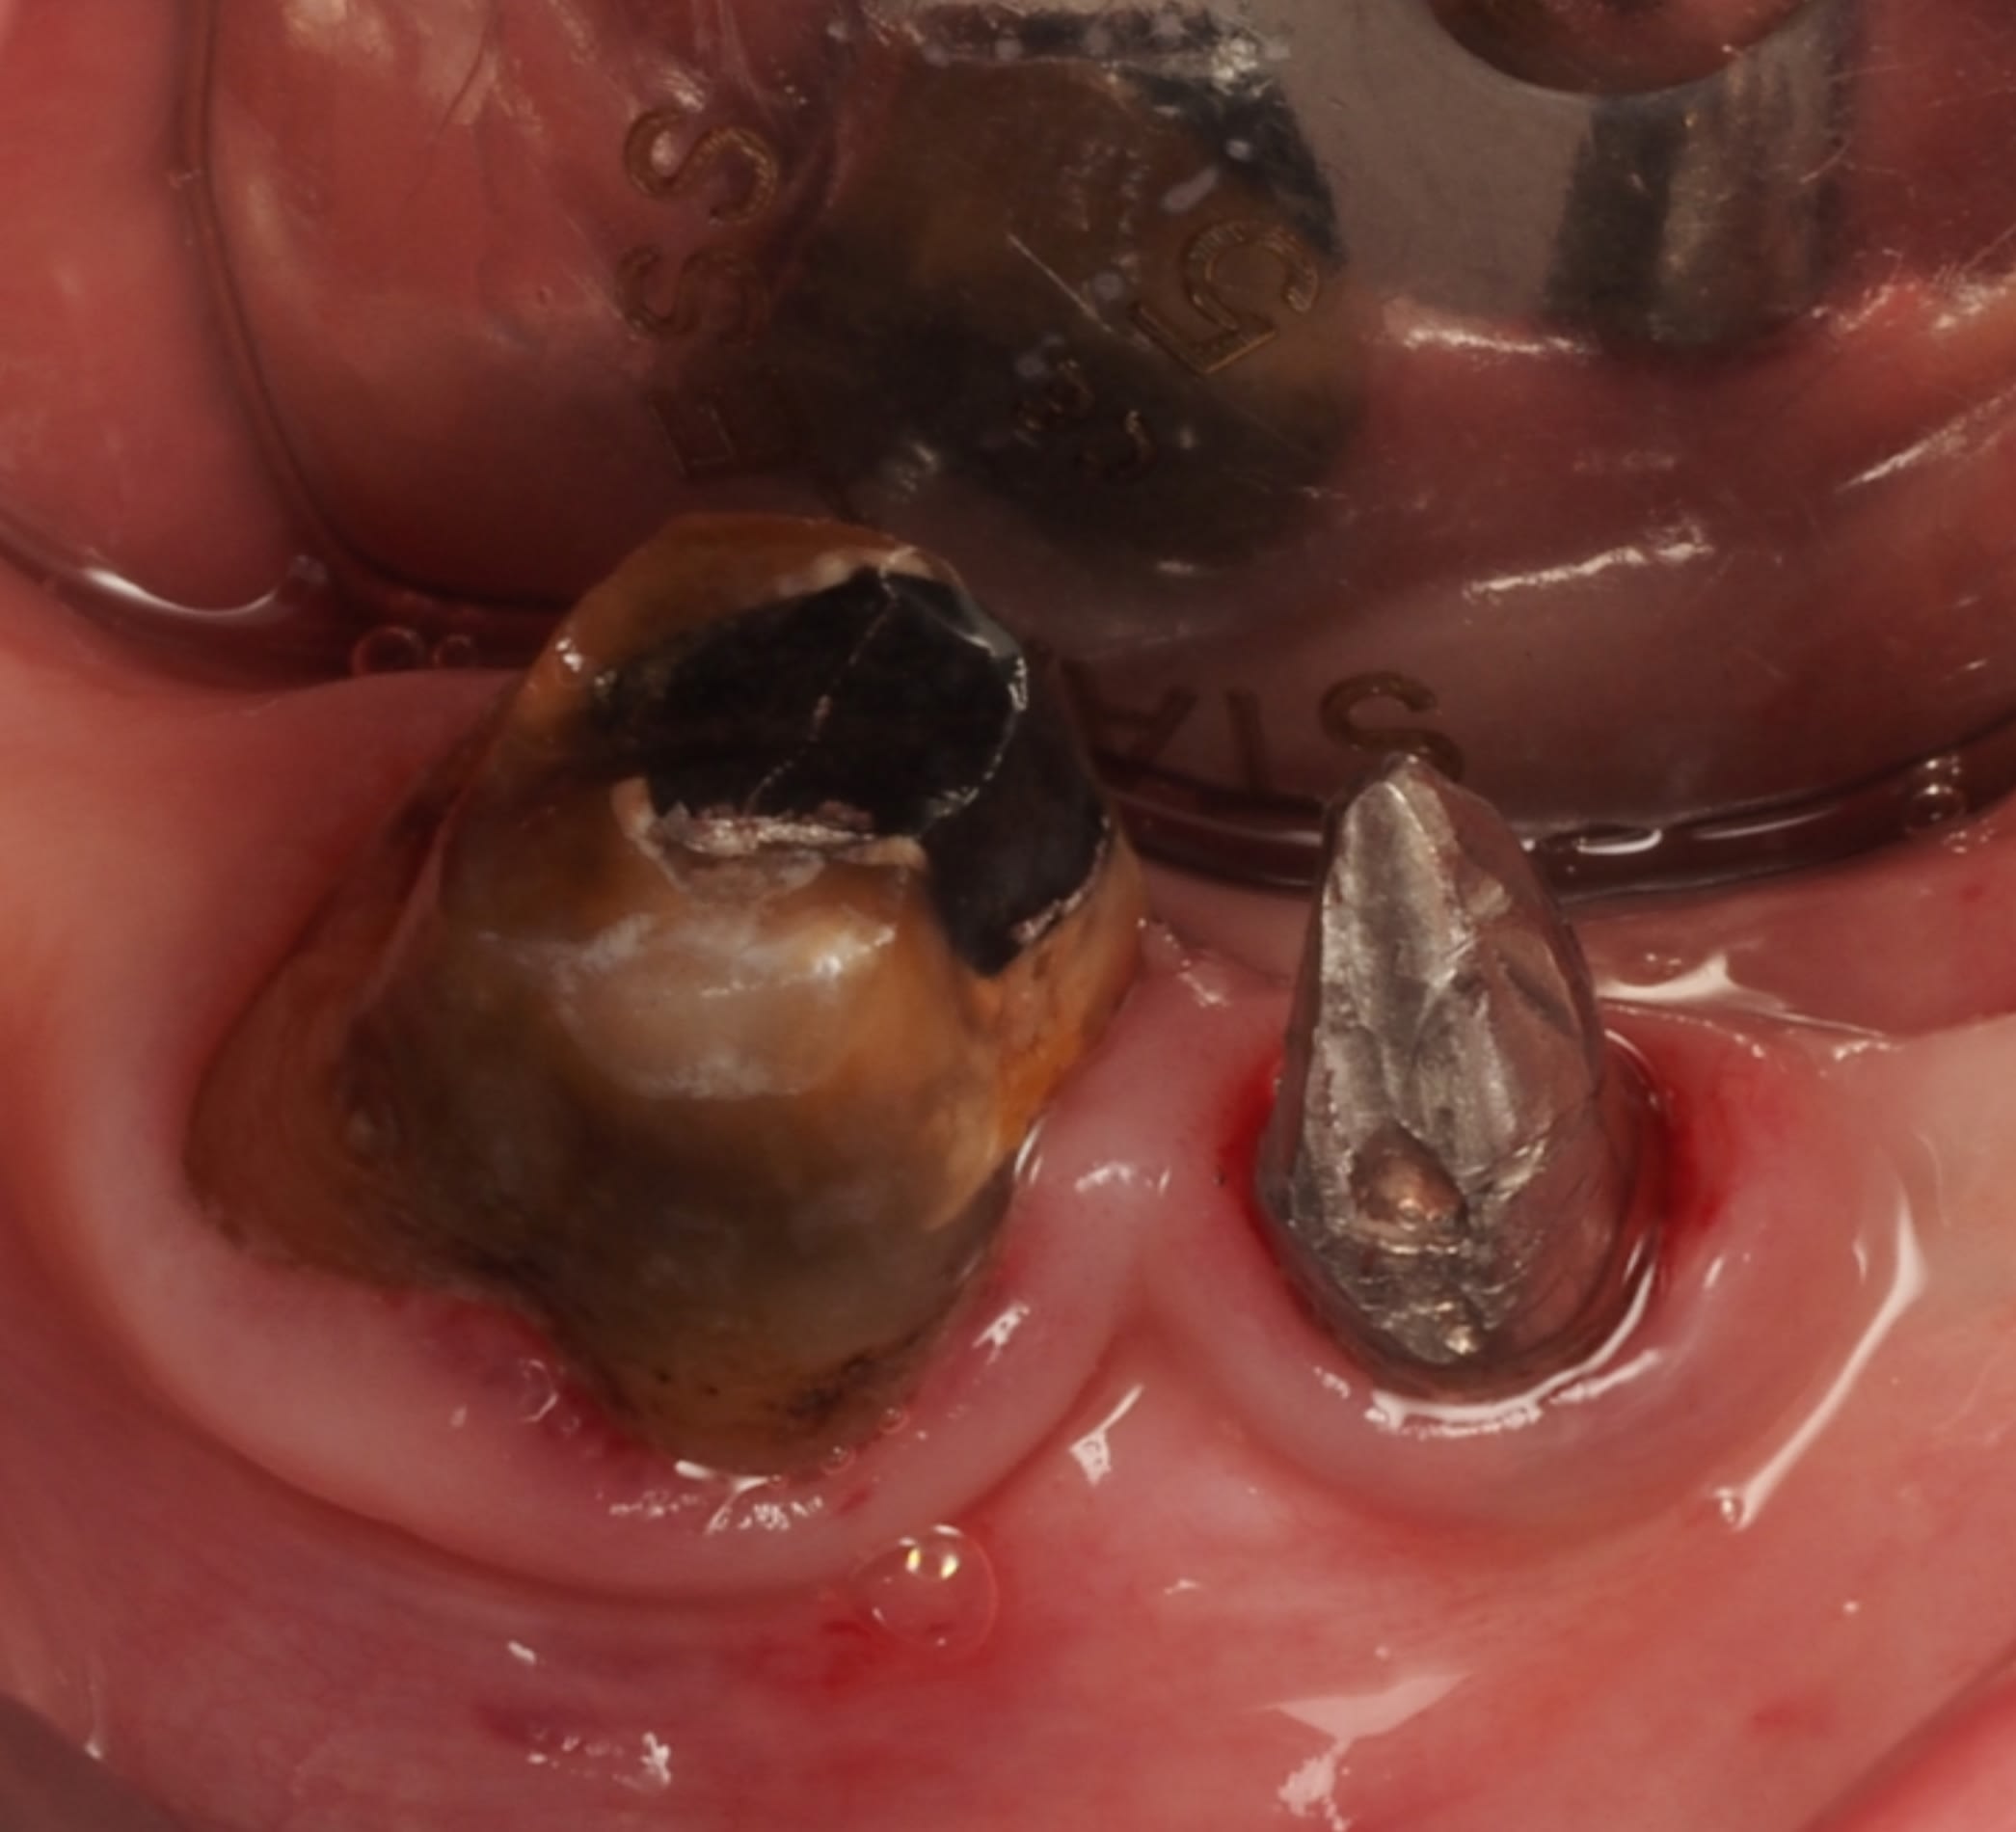

Voilà ce qu'il y avait en dessous, impossible de trouver le puits de vissage du "pilier"...

J'ai rescellé au temp bond en attendant l'acceptation du devis pour ROG / GEC / implant 35 et nouvelles couronnes 36/35 (la couronne sur 37 sera refaite chez un confrère omni)